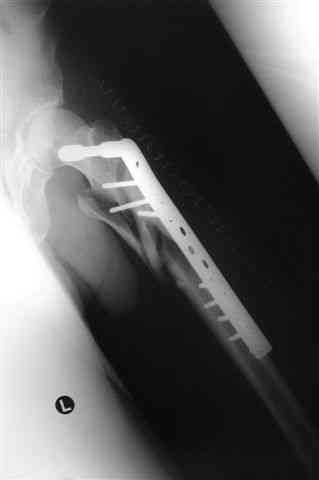

Бедро фиксировал длинной DCS.

По типу бриджинг плэйтин, крюком удалось низвести малый вертел и фиксировать винтом для восстановления медиальной стенки.

> Бедро фиксировал длинной DCS.

А почему не гвоздем закрыто?

ET>> Бедро фиксировал длинной DCS.

AC>А почему не гвоздем закрыто?

Изначально планировался длинный гамма гвоздь , но набор заказывается обычно из Йоханнесбурга, а в этот раз все совпало с новогодними празднованиями и вся жизнь была *парализована* новогодней фиестой:-((, поэтому безуспешно прождав 3-4-5 дней обещанной доставки зафиксировал пластиной- жаль, что так всй случилось У местного

Страйкера сервис ненавязчивый :-))

В приложении отправляю послеопер. снимки бедра и лодыжки обсуждаемого вчера больного.